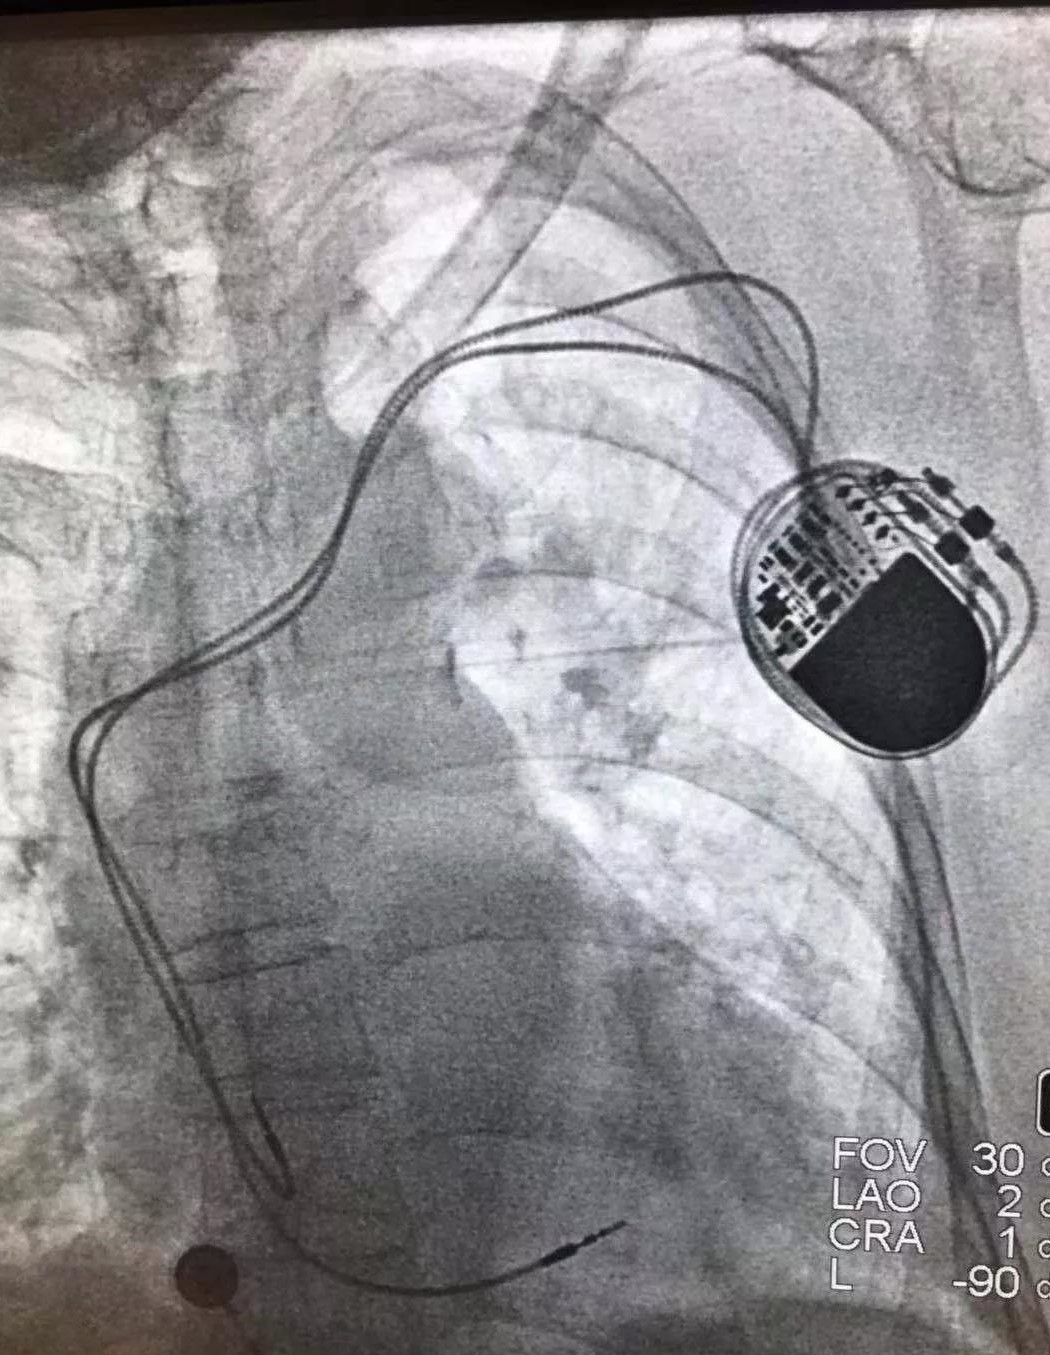

近日,四川省成都大学附属医院心内科顺利地为一名心动过缓的患者植入了新型国产自动化芯彤心脏起搏器。

该患者为89岁高龄女性,反复头晕、乏力等入院,心电图表现为持续的III度房室传导阻滞,结性逸搏、室性逸搏同时存在,白天最低心率40±次/分,查体一般情况尚可,无心力衰竭症状与体征。入院诊断III度房室传导阻滞,拟行起搏器植入术,经过仔细术前评估,详细解释起搏器植入的必要性、相关风险及术后注意事项等,患者及家属同意接受手术,我科成功为该患者植入新型国产自动化芯彤心脏起搏器。

芯彤起搏器不仅价格低于进口产品,医保报销比例也非常高,具有电极全,有保障的特点。经过详细的术前评估,在何川主任的带领下,心内科团队密切配合成功为该患者完成了起搏器植入手术,手术过程非常顺利,患者植入7天后伤口愈合良好,目前已出院,回归正常生活。

此次为患者植入的芯彤心脏起搏器,是基于美敦力公司先进的起搏器技术和质量标准由深圳彩神在线网信彩票-彩神通免费版下载-彩神8争霸vlll-彩神购彩购彩大厅-彩神软件陆立根免费版-彩神ll争霸3-彩神ll彩神8-彩神ll争霸彩票-拼搏在线彩神网网页版科技生产的国产起搏器,具有电极全,有保障的特点,拥有配套主动和被动电极,由美敦力公司提供技术支持与服务,医生和患者在使用国产起搏器的同时,可享受到进口产品的服务。另外具有1.3Ah大电池容量,长寿命,心室心房自动阈值管理等特点。